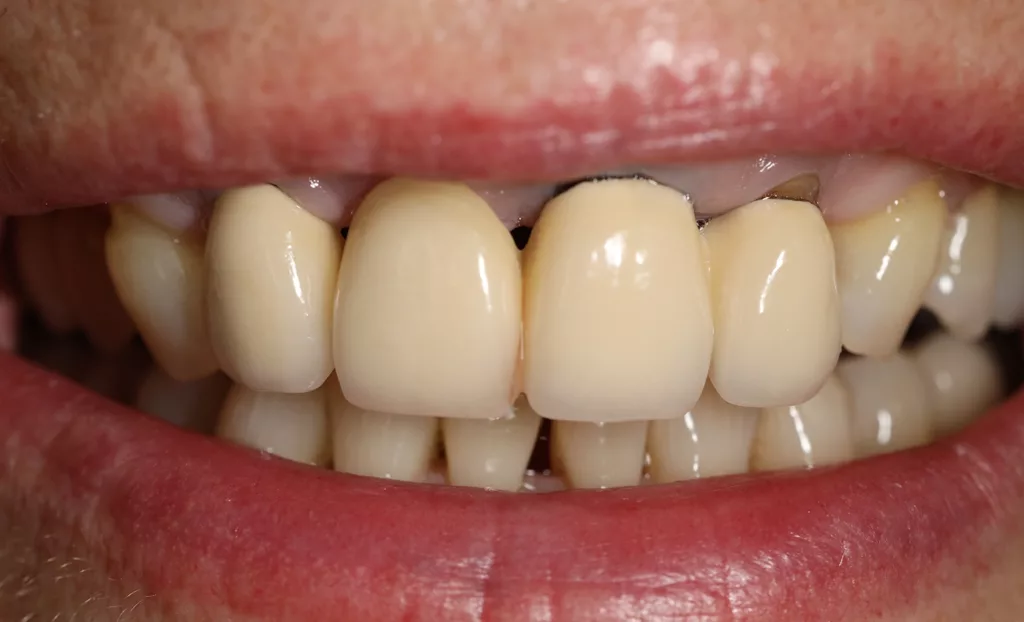

Eine 63-jährige Patientin wurde in der Zahnarztpraxis vorstellig, weil sie mit der Ästhetik ihrer erst vier Jahre alten Brückenversorgung in der Oberkieferfront unzufrieden war. Bei der klinischen Untersuchung zeigte sich eine leblos wirkende VMK-Brücke von 12 auf 21 und 22. Die Kronen wirkten unförmig und unruhig. Die metallischen Kronenränder an den Pfeilerzähnen und ein Zahnhalsdefekt an 22 wurden beim Lächeln sichtbar (Abb. 1 und 2). Die Entscheidung fiel auf eine vollkeramische Neuversorgung mit einem Gerüst aus dem Zirkoniumdioxid VITA YZ HT und einer minimalen Verblendung mit VITA LUMEX AC, um morphologisch schlanker zu werden und trotzdem ein lebendiges Farb- und Lichtspiel zu implementieren.